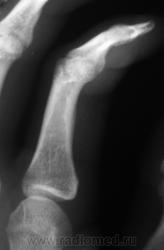

Травма. Пациент направлен на рентгенографию 2 пальца.

Вот это прикол. Настоящая головоломка !!! это инородное тело в области мед края головки осн фаланги 2 пальца.

Если не ошибаюсь, конечно. Заметить такое - респектищеее!

Ну, не знаю. я тоже ничего не вижу. А тонюсенькая полосочка может быть и артефактом.

Валентин Львович, вы ж укажите, где локальная болезненность. Может перелом основания осн. фаланги?

Участок максимальной болезненности.

??? Головка ср.ф. какая-то скошенная, но деструктивн. изм., повреждений не вижу.

Меня тоже смутила форма головки фаланги.